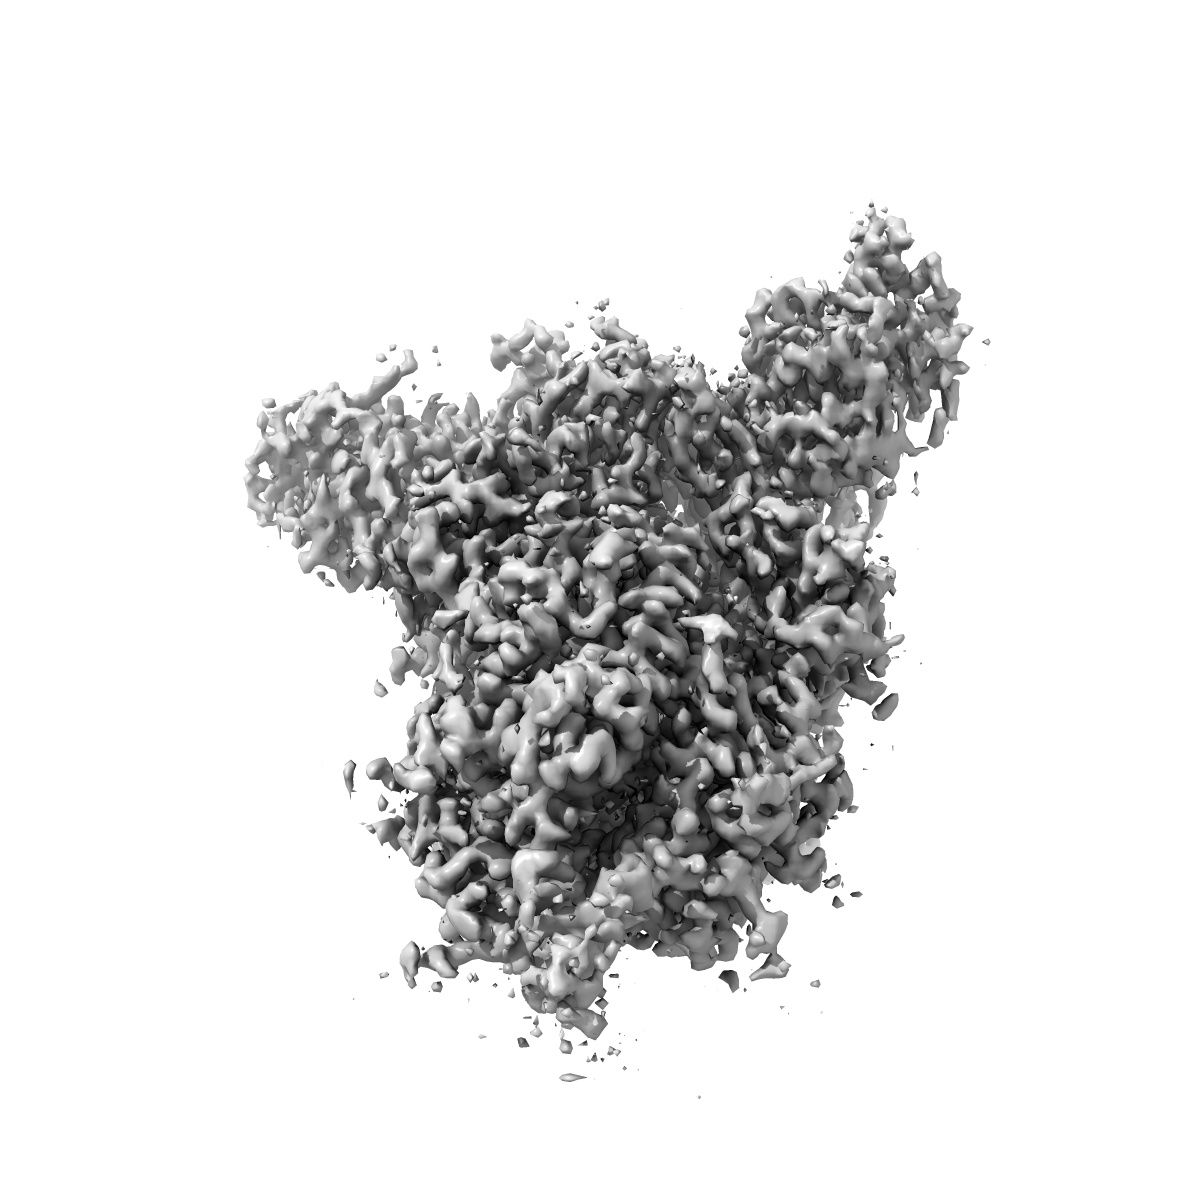

S protein of SARS-CoV-2 in the locked conformation

Sample: S protein of SARS-CoV-2 in the locked conformation

Structural basis for the different states of the spike protein of SARS-CoV-2 in complex with ACE2.

Yan R, Zhang Y, Li Y , Ye F , Guo Y , Xia L, Zhong X, Chi X, Zhou Q

(2021) Cell Res , 31 , 717 - 719